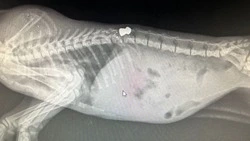

Котенок, который пострадал от человеческой жестокости и едва не погиб из-за пули, выпущенной ему прямо в позвоночник, наконец обрел настоящую семью. Малышку Инь приютила сотрудница ветеринарной клиники, где лечили животное. Вместе с тем врач успешно вызволила пулю из тела молодой кошки.